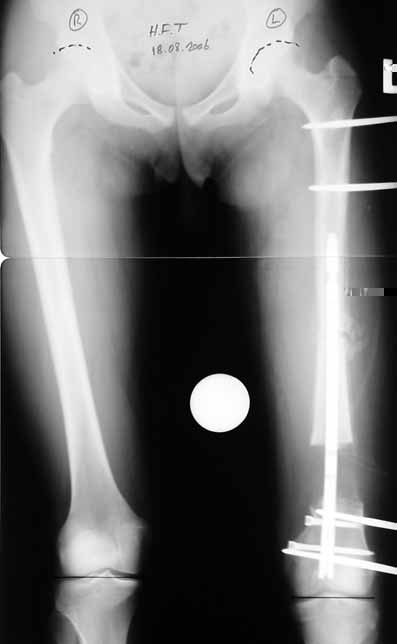

3. POSTTRAUMATIC LOWER LIMB SHORTNESS (MALUNION)

This type of shortness occurs after a fracture heals in a shortened position. Most cases are seen in adults and can be treated with one lengthening operation. Additional deformities can be corrected simultaneously. Most of these cases can be treated with lengthening over nail or just corrections and intramedullary nailing.